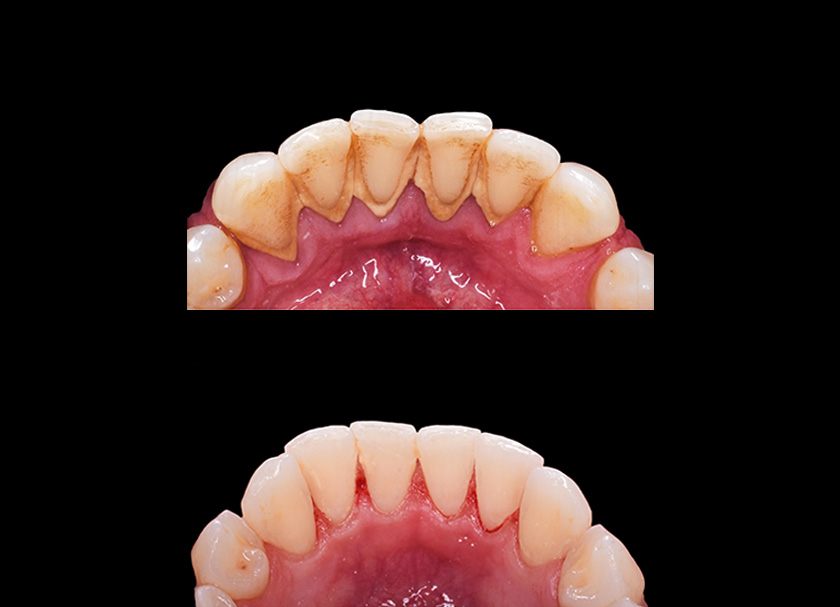

In this process, the plaque and tartar from your teeth are removed. Our dentists are very thorough, and they remove the deposits along the gumline of the teeth, smoothening your teeth so that it attaches to the gums.

Beverages like tea, coffee, and wine stain your teeth. Scaling helps remove these pigments from your teeth to a great extent and gives you an attractive smile.

Plaque is a breeding ground for bacteria, and it develops into tartar. Tartar and plaque deposits on your teeth result in halitosis or bad breath. Daily brushing and flossing will only give you partial results, and only teeth scaling will completely rid your mouth of plaque and tartar, eliminating bad breath simultaneously.